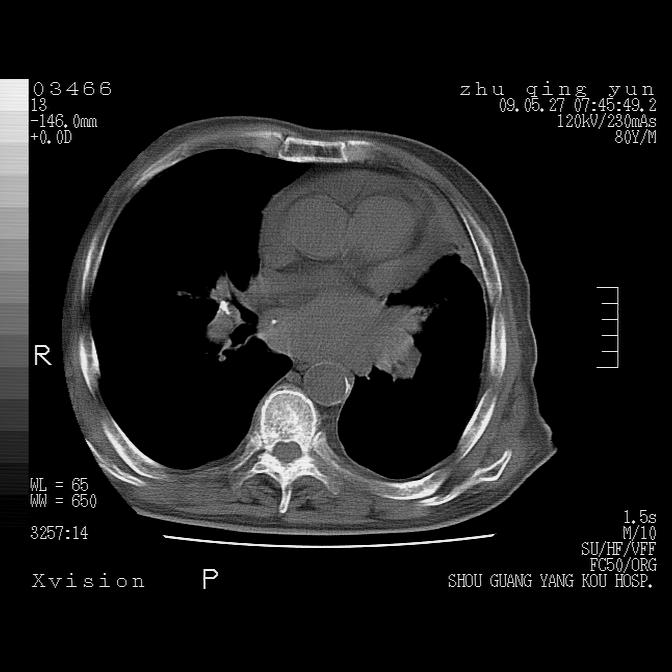

病人男性,年龄80,气喘来院,其他病史不太详细,1月前有过恶心,呕吐,在当地人民医院做过钡餐,诊断胃炎,

1)考虑左肺中央型肺癌并阻塞性肺炎,后下纵隔受侵伴纵隔淋巴结转移。2)双侧少量胸腔积液,胸膜增厚。3)心包积液。

左肺下叶见多发片状及结节状病灶,左肺基底段支气管闭塞,纵隔内见多发淋巴结肿大,纵隔向左侧移位,左侧胸廓变小。应该是左肺下叶中心型肺癌,纵隔淋巴结转移,左侧肺内转移,左肺基底段肺不张,阻塞性肺炎。

1)考虑左肺中央型肺癌并左肺下叶阻塞性肺炎、不张;左胸膜腔积液、心包积液、纵隔淋巴结转移;癌肿累及左心房。2)左心室大。冠状动脉壁钙化斑。

1)考虑左肺中央型肺癌并左肺下叶阻塞性肺炎、不张;左胸膜腔积液、心包积液、纵隔淋巴结转移;癌肿累及左心房。